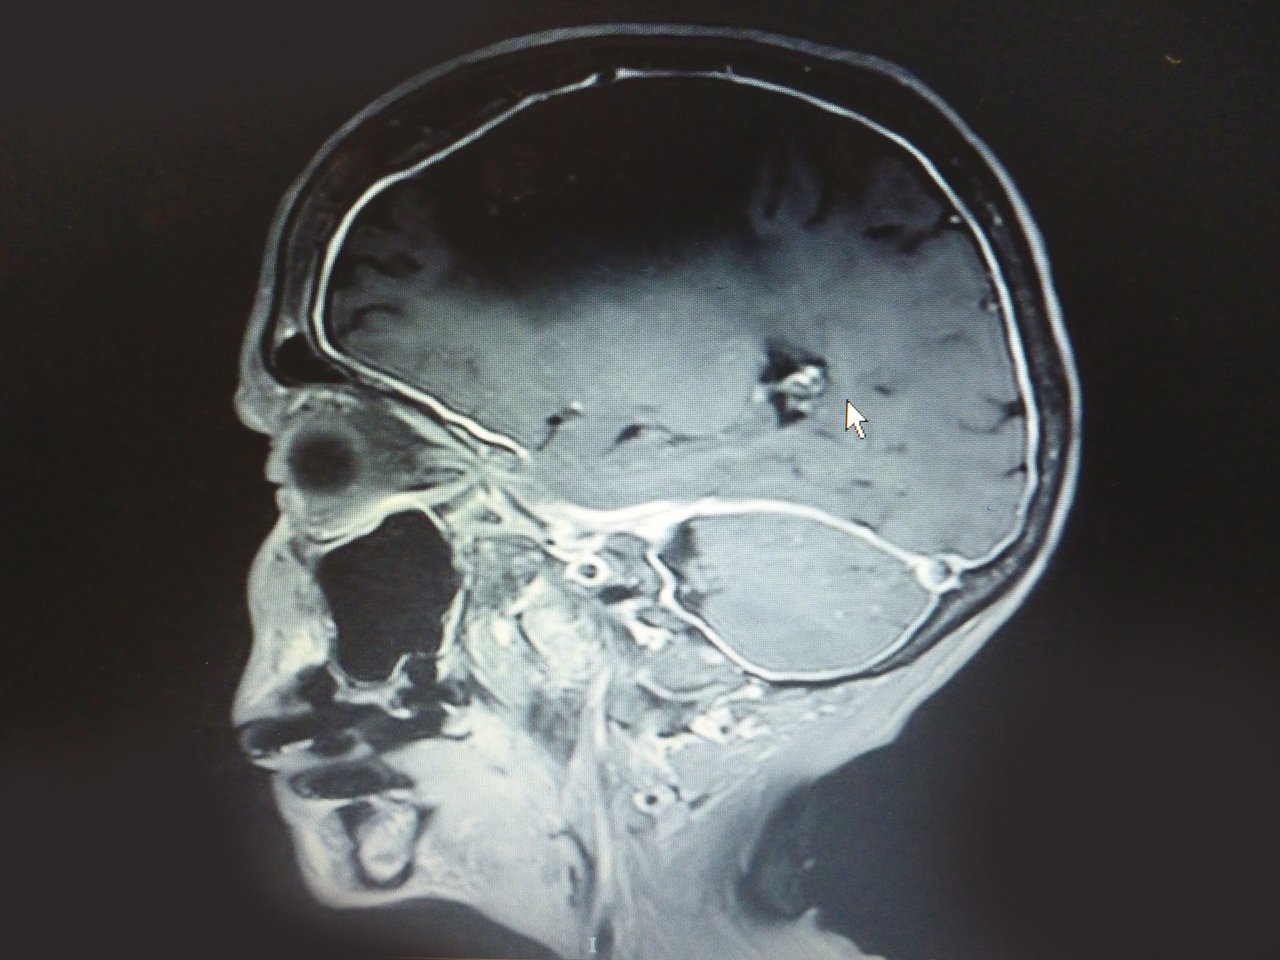

Quel est votre diagnostic ? Leptoméningite Pachyméningite Il s'agit d'une pachyméningite. Pour en savoir plus : Ducros A. Céphalées aiguë et chronique. Rev Prat 2006;56(19):2161-72. Méningiome Méningoencéphalite Hydrocéphalie OK Valider mes réponses